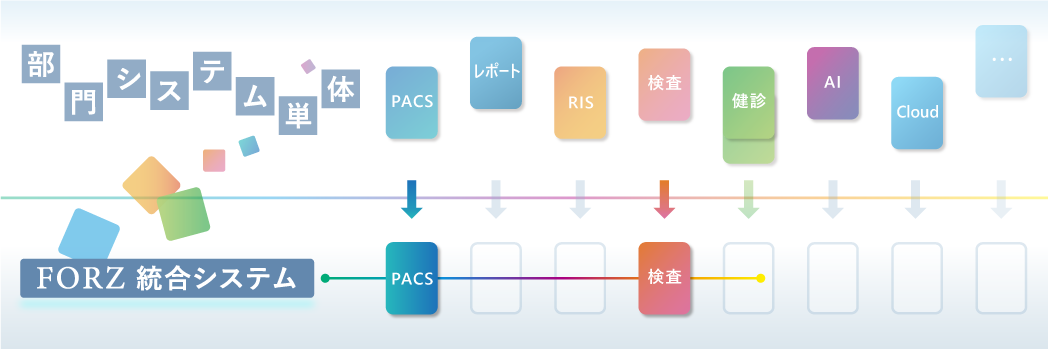

データバックアップサービス 画像ファインリングシステム PACS

画像ファインリングシステム PACS 放射線情報管理システム

放射線情報管理システム レポートシステム

レポートシステム 検査システム

検査システム 健診システム

健診システム FORZ-HWS(クラウドサービスシステム)

FORZ-HWS(クラウドサービスシステム)